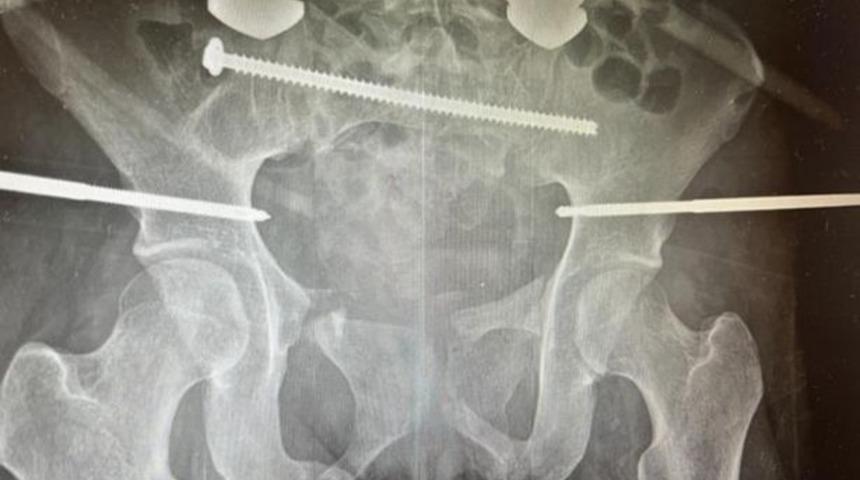

Geçen yıl ağustos ayında bir lunaparkta geçirdiği kazanın ardından, Chloe sağ bacağında ve pelvisinde ciddi kırıklarla hastaneye kaldırıldı. Doktorlar, bunun görülebilecek en korkunç pelvik kırık olduğunu ve Chloe'nin orada öleceğini düşündüler. Ancak bekledikleri gibi olmadı.

Genç kadın, 90 günü hastanede geçirdi. 22 gün komada kalan Chloe, hayat kurtaran birçok zorlu ameliyat geçirdi. Sonrasında ise tekrar yürümeyi öğrenmesini de içeren zorlu bir iyileşme sürecine girdi.